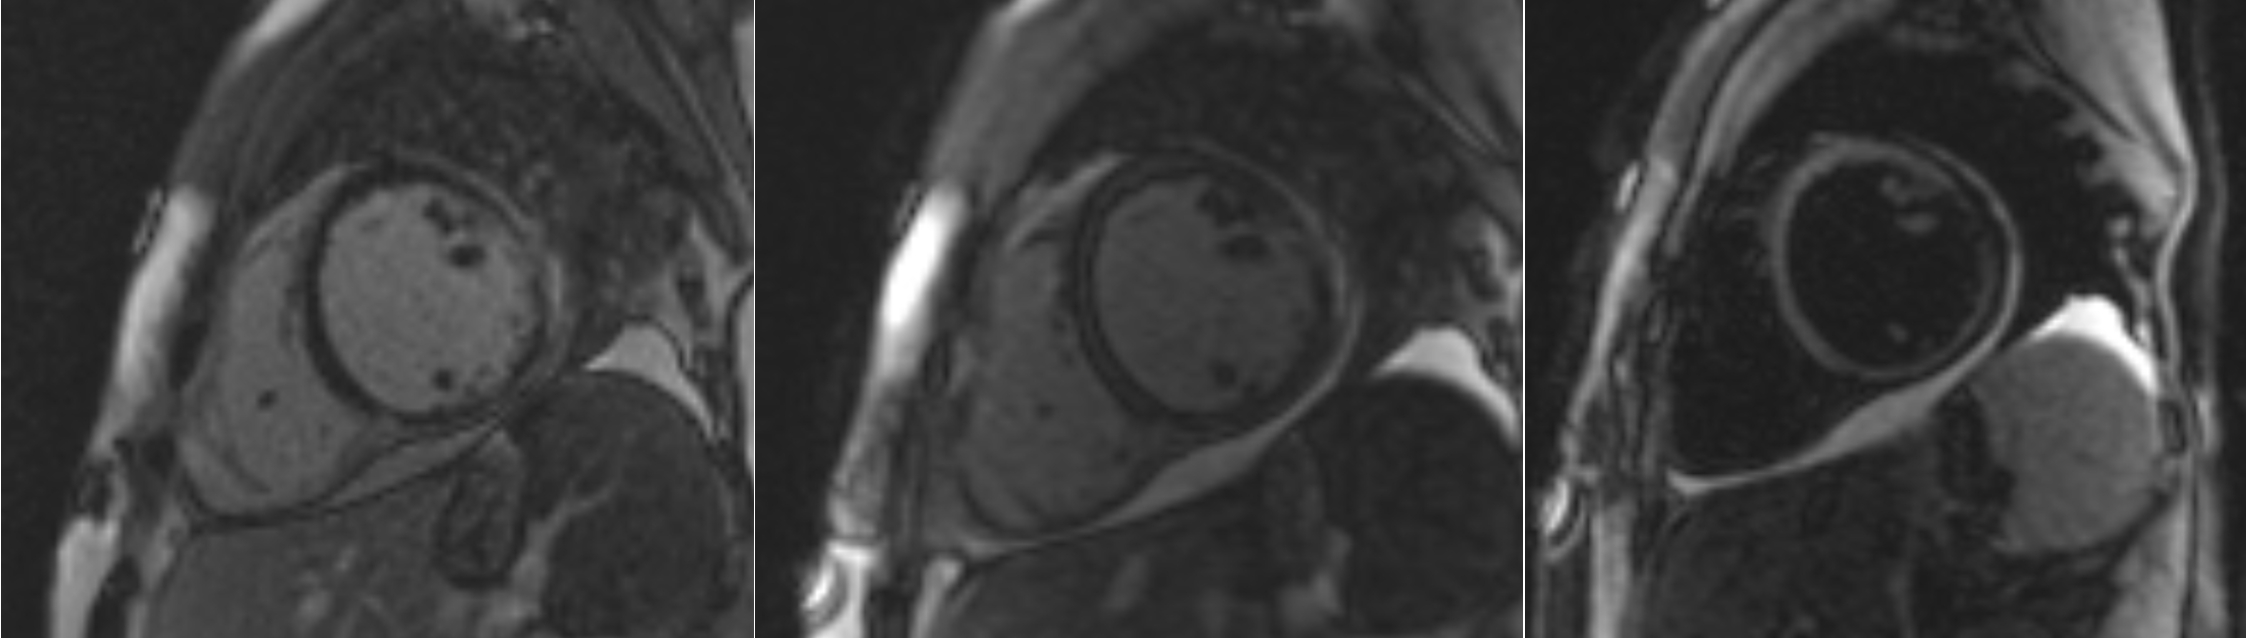

A 21-year-old female with history of sustained ventricular fibrillation (VT) at age 18, VT arrest at age 20,dilated cardiomyopathy with LVEF 30-35% and subcutaneous ICD, who was admitted after multiple ICD defibrillations. Device interrogation demonstrated 23 monomorphic VT episodes treated with 44 shocks by the ICD. Coronary angiogram demonstrated non-obstructive coronary arteries. Patient underwent VT ablation, complicated by incessant VT from LV summit which was eliminated during procedure. Cardiac MRI demonstrated RVEF 33%, regional dyskinesis in the sub-tricuspid area and RV outflow tract. cMRI also demonstrated subepicardial late gadolinium enhancement at the level of the mid antero/infero lateral walls with extension into the apicolateral wall and mid inferoseptal territory. These findings heightened suspicion for left ventricle fatty infiltration. However, endomyocardial biopsy negative for inflammation or granuloma, no fibrosis, negative iron and amyloid staining. Left-dominant arrhythmogenic cardiomyopathy was diagnosed based on cMRI findings, LV systolic dysfunction, and arrhythmia of LV origin. Subcutaneous ICD was explanted and replaced with a dual chamber ICD. Patient was discharged on Mexiletine and GDMT for HFrEF. Genetics testing later revealed rare co-occurance of two genetic mutations including MYBPC3 and DSP.